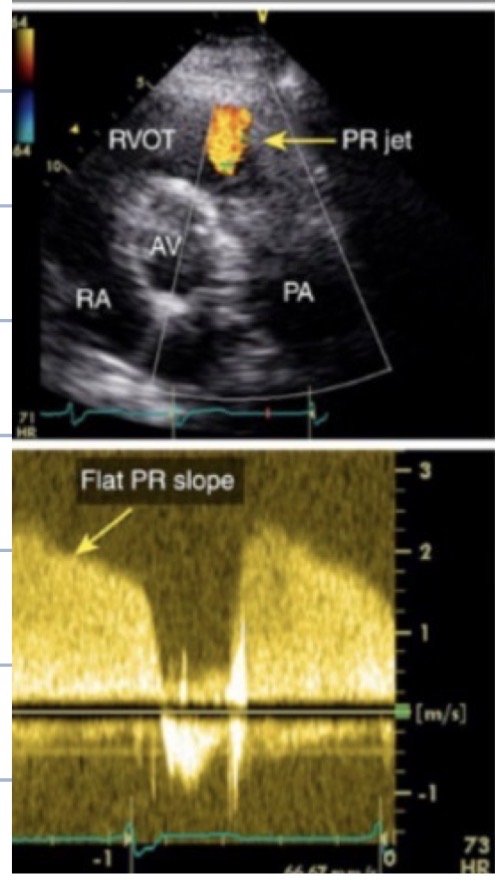

Mild to Moderate

What grade of PR is this

Severe PR

The steeper the slope, the more severe the PR

How does slope seen on CW indicate pulmonic regurgitation